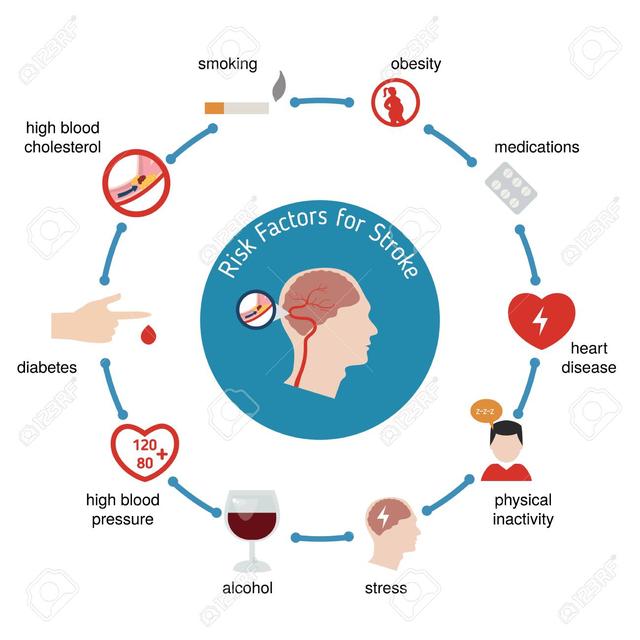

De nombreux facteurs augmentent le risque d'infarctus cérébral, qu'il s'agisse d'un accident ischémique transitoire et d'un infarctus cérébral léger ou d'un infarctus cérébral complet. Parmi les facteurs de risque sur lesquels il est possible d'intervenir, on peut citer

●Facteurs de risque liés au mode de vie :Il s'agit par exemple de l'obésité ou du surpoids, de l'inactivité physique, de l'abus d'alcool, du tabagisme et du tabagisme passif, ainsi que de la consommation de drogues illicites telles que la méthamphétamine et la cocaïne.

●Facteurs de risque des maladies médicalesLes maladies cardiovasculaires : par exemple l'hypertension, l'hypercholestérolémie, le diabète, les maladies cardiovasculaires (par exemple la fibrillation auriculaire, les maladies coronariennes), l'apnée obstructive du sommeil (ronflement), l'hyperhomocystéinémie.

D'autres facteurs de risque plus élevés sont

●L'âge :Les personnes âgées de 55 ans ou plus sont plus exposées que les jeunes.

●Genre :Le risque d'accident vasculaire cérébral est plus faible chez les femmes que chez les hommes. Cependant, les femmes sont généralement plus âgées lorsqu'elles sont victimes d'un accident vasculaire cérébral, ce qui les rend plus susceptibles de mourir d'un accident vasculaire cérébral que les hommes.

●Hormones :Les médicaments qui augmentent le taux d'œstrogènes augmentent le risque.